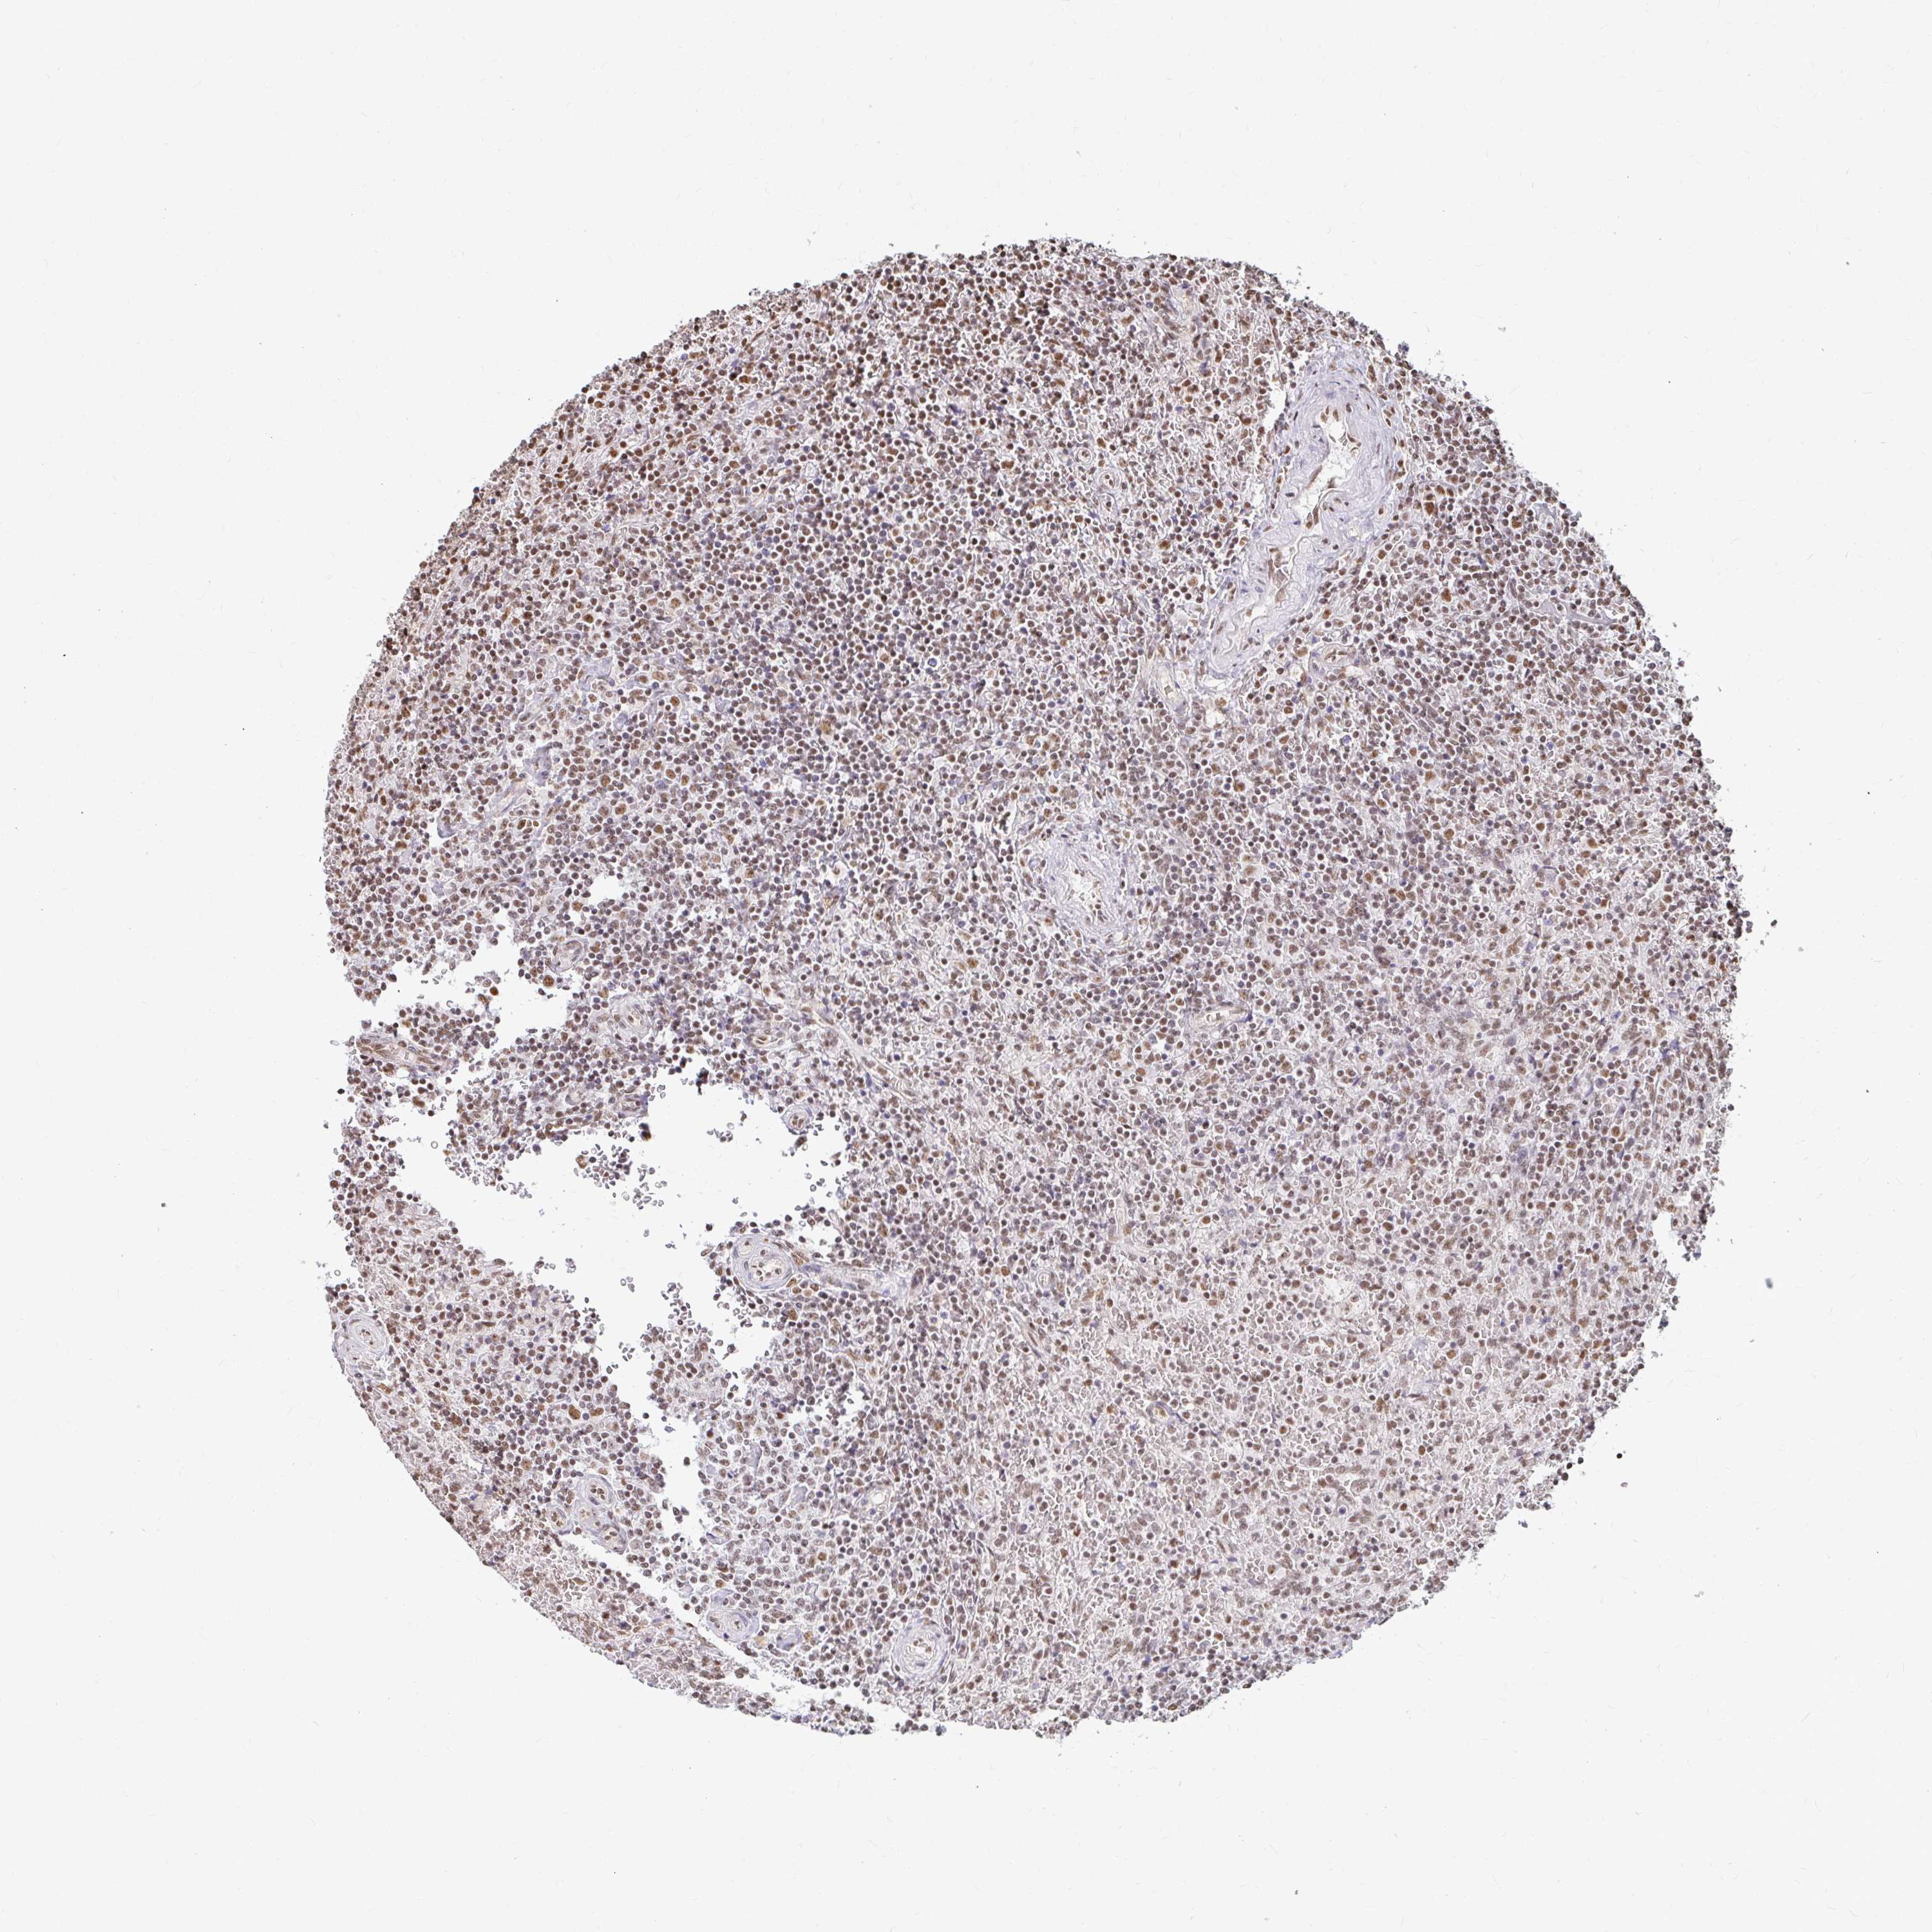

LYMPHOMA - Protein expressioni

A mouse-over function shows sample information and annotation data. Click on an image to view it in a full screen mode. Samples can be filtered based on level of antibody staining by selecting one or several of the following categories: high, medium, low and not detected. The assay and annotation is described here.

Each image is clickable and will lead to virtual microscopy that enables deeper exploration of all samples and also displays staining intensity scores, fraction scores and subcellular localization as well as patient and tissue information for each sample.

Antibody HPA058707

Staining

High

Medium

Low

Not detected

Intensity

Strong

Moderate

Weak

Negative

Quantity

>75%

75%-25%

<25%

None

Location

Nuclear

Cytoplasmic/membranous

Cytoplasmic/membranous,nuclear

Malignant lymphoma, non-Hodgkin's type, High grade